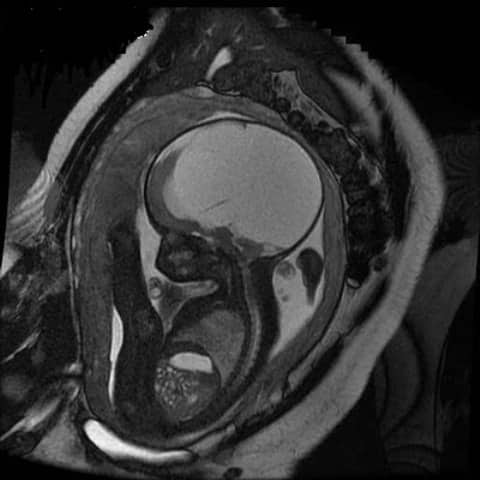

Ở giai đoạn 3 tháng giữa thai kỳ, nếu trong quá trình siêu âm phát hiện não thất thai nhi bị giãn với đường kính là 10 – 15mm được gọi là giãn não thất, còn đường kính trên 15mm tức là thai nhi đã bị não úng thủy.

Lúc này, cần chẩn đoán và theo dõi của siêu âm rõ ràng. Nếu siêu âm phát hiện não thất có kích thước trên 15mm thì rất đáng lo ngại. Do đó, khi phát hiện cần kiểm tra và siêu âm kỹ đồng thời với tìm các tổn thương khác trên tim và não của thai nhi.